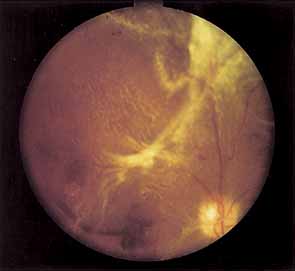

Two types of diabetic retinal detachments occur, those that are caused by traction alone (nonrhegmatogenous) (Fig. 14), and those caused by retinal break formation (rhegmatogenous) (Figs. 15 and 16). Characteristics of nonrhegmatogenous (traction) detachment in PDR include the following: (1) the detached retina is usually confined to the posterior fundus and infrequently extends more than two-thirds of the distancd to the equator, (2) it has a taut and shiny surface, (3) it is concave toward the pupil, and (4) there is no shifting of subretinal fluid.

Fig. 14 Traction retinal detachment. The detached retina has a smooth noncorrugated appearance and is convex toward the pupil.

Fig. 15 Combined traction/rhegmatogenous retinal detachment. The detached retina has a corrugated appearance and is concave toward the pupil.

Fig. 16 Round hole near fibrous proliferation.

Vitreous traction may also cause focal areas of retinoschisis that may be difficult to distinguish from full-thickness traction retinal detachment. In retinoschisis the elevated layer is thinner and more translucent (Fig. 17).

In combined traction/rhegmatogenous detachment, the borders of the elevated retina usually extend to the ora serrata; the retinal surface is dull and grayish and undulates because of retinal mobility caused by shifting subretinal fluid. The causative retinal breaks are usually found in the posterior pole near areas of fibrovascular proliferation. They are oval in shape and appear to be partly the result of tangential traction from the proliferative tissue as well as vitreous traction. Determining the location of retinal holes may be complicated by many factors, particularly poor dilation of the pupil, lens opacity, increased vitreous turbidity, vitreous hemorrhage, intraretinal hemorrhage, and obscuration of the breaks by overlying proliferative tissue. Often they are only located during vitrectomy surgery.